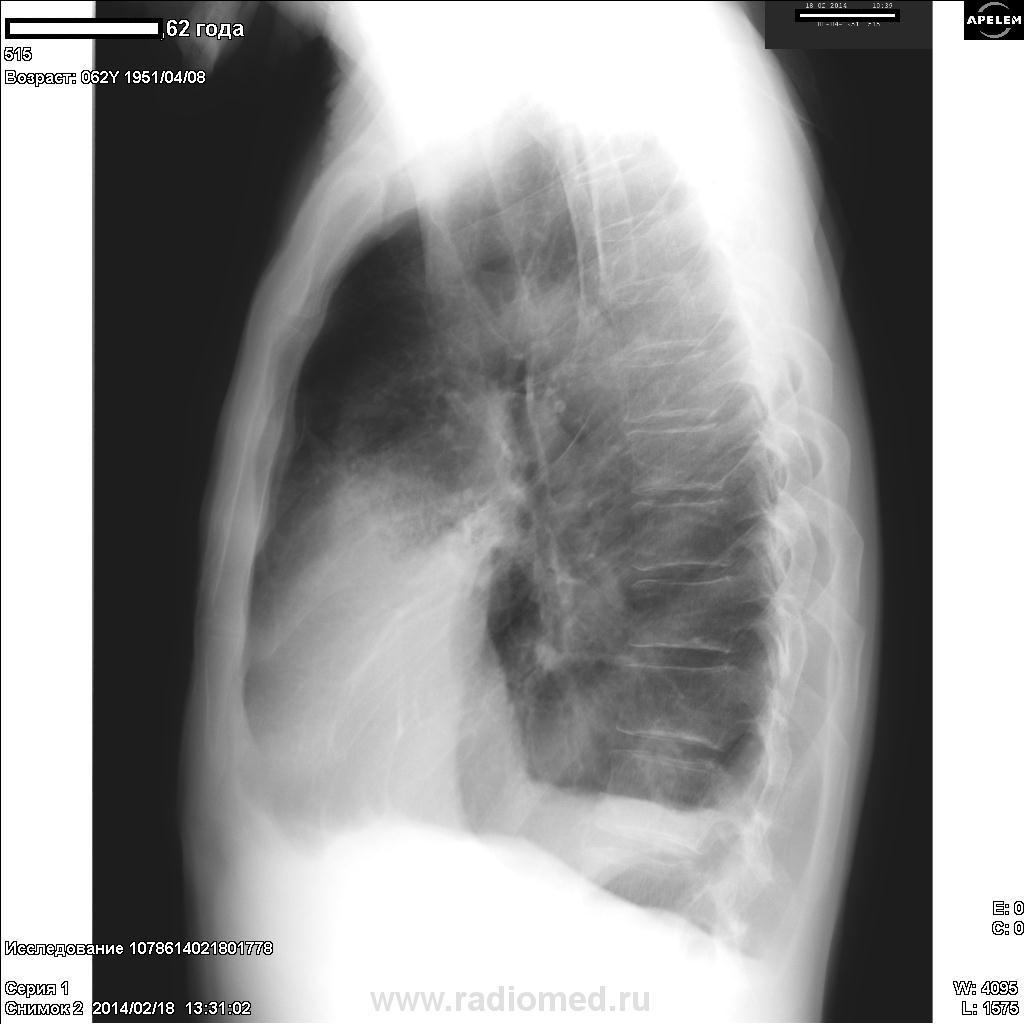

Пациент, 62 года. Жалобы на слабость, отсутствие аппетита, небольшой кашель с мокротой, боли в грудной клетке слева. Болен 5-й день после «промокли ноги на рыбалке». Температура – 37, 8 гр. Р-архива нет. Болел последний раз лет 30 назад. Какие будут мнения?

Может, начать с пневмонии в язычковых сегментах слева, осложнённой гидротораксом. Ателектаз S 7. После противовоспалительнеой терапии - Р-контроль. Картина может измениться.

Слева корень какой-то "некакой", ателектаз в язычках. Я уверен, у вас в рукаве томограммы... Флюорографию, видиммо, тоже 30 лет назад проходил?

Я бы онкологию в первую очередь начала исключать.

Да нет, ребят, какая пневмония? В первую очередь, рак

Осумкованный выпот, инфильтрация. Не очень ясно, что там в левом корне - смотрится как образование

Коллега, Вы же понимаете, что рак тут, скорее верхнедолевого с переходом на средне, частично нижне.